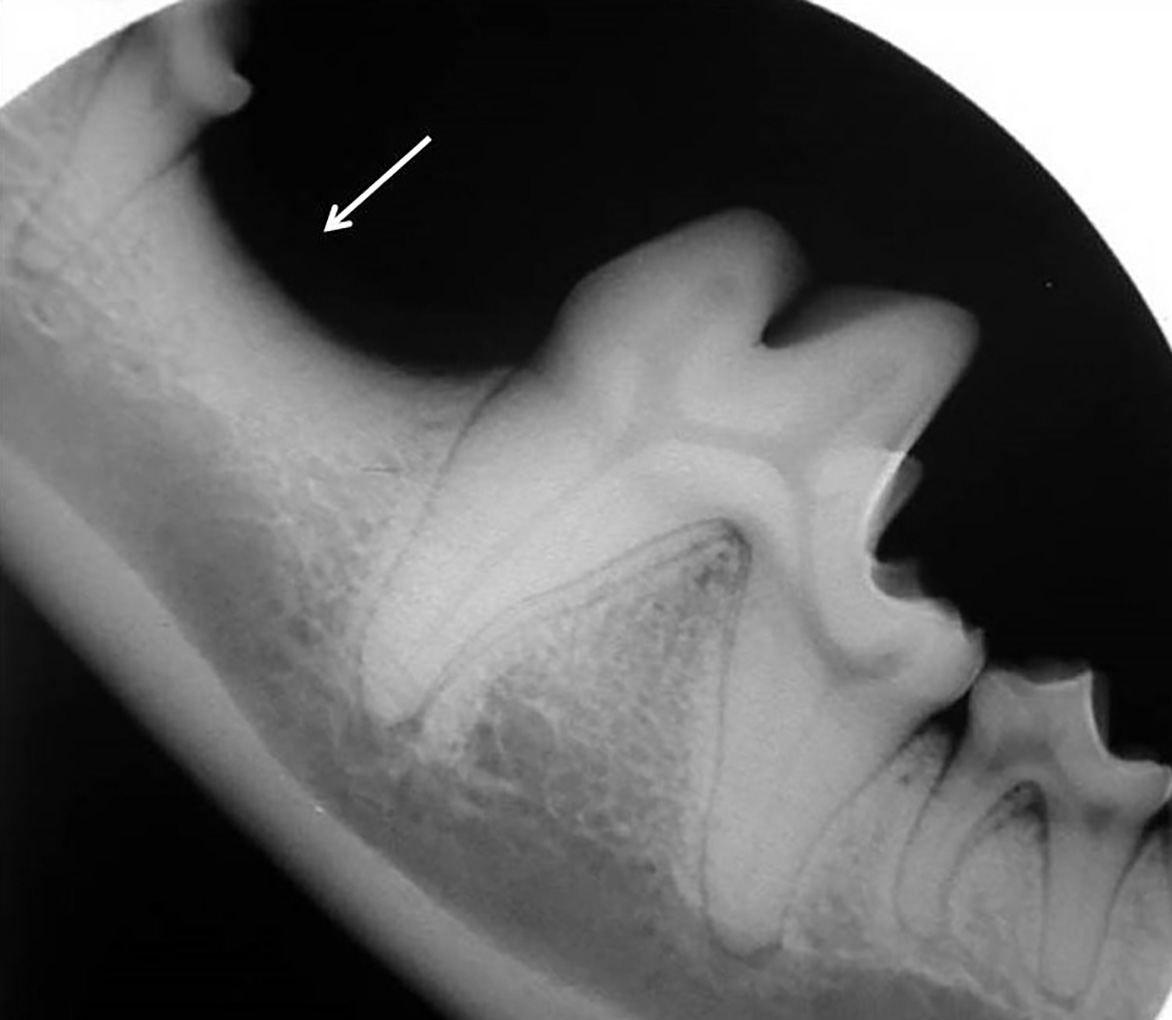

Además de permitirnos evaluar el grado de enfermedad periodontal, también hace posible seleccionar el mejor tratamiento en función de su patología y las posibles complicaciones, como las fracturas mandibulares iatrogénicas en perros de talla pequeña con enfermedad periodontal PD4 (imágenes 10 y 11).